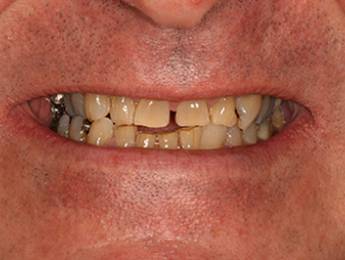

6. Eset

Nagymértékű fogkopás, erózió, csikorgatás a teljes rágóapparátust túlterhelve okoz reménytelennek tűnő helyzeteket.

Ebben az esetben implantátumok , koronák és hidak segítségével változtattunk a páciens fogainak érintkezésén. 6 hónapig ideiglenes hidakkal teszteltük a megváltoztatott harapási pozíciót. Ezután készültek el a végleges fix pótlások.